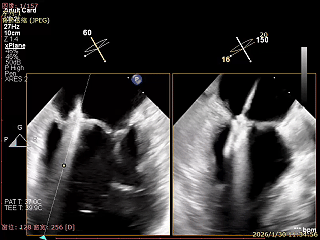

夹子释放后,反流基本消失

LVOT切面可见主瓣二尖瓣术后反流基本消失

植入两枚夹子后二尖瓣平均跨瓣压差2mmHg